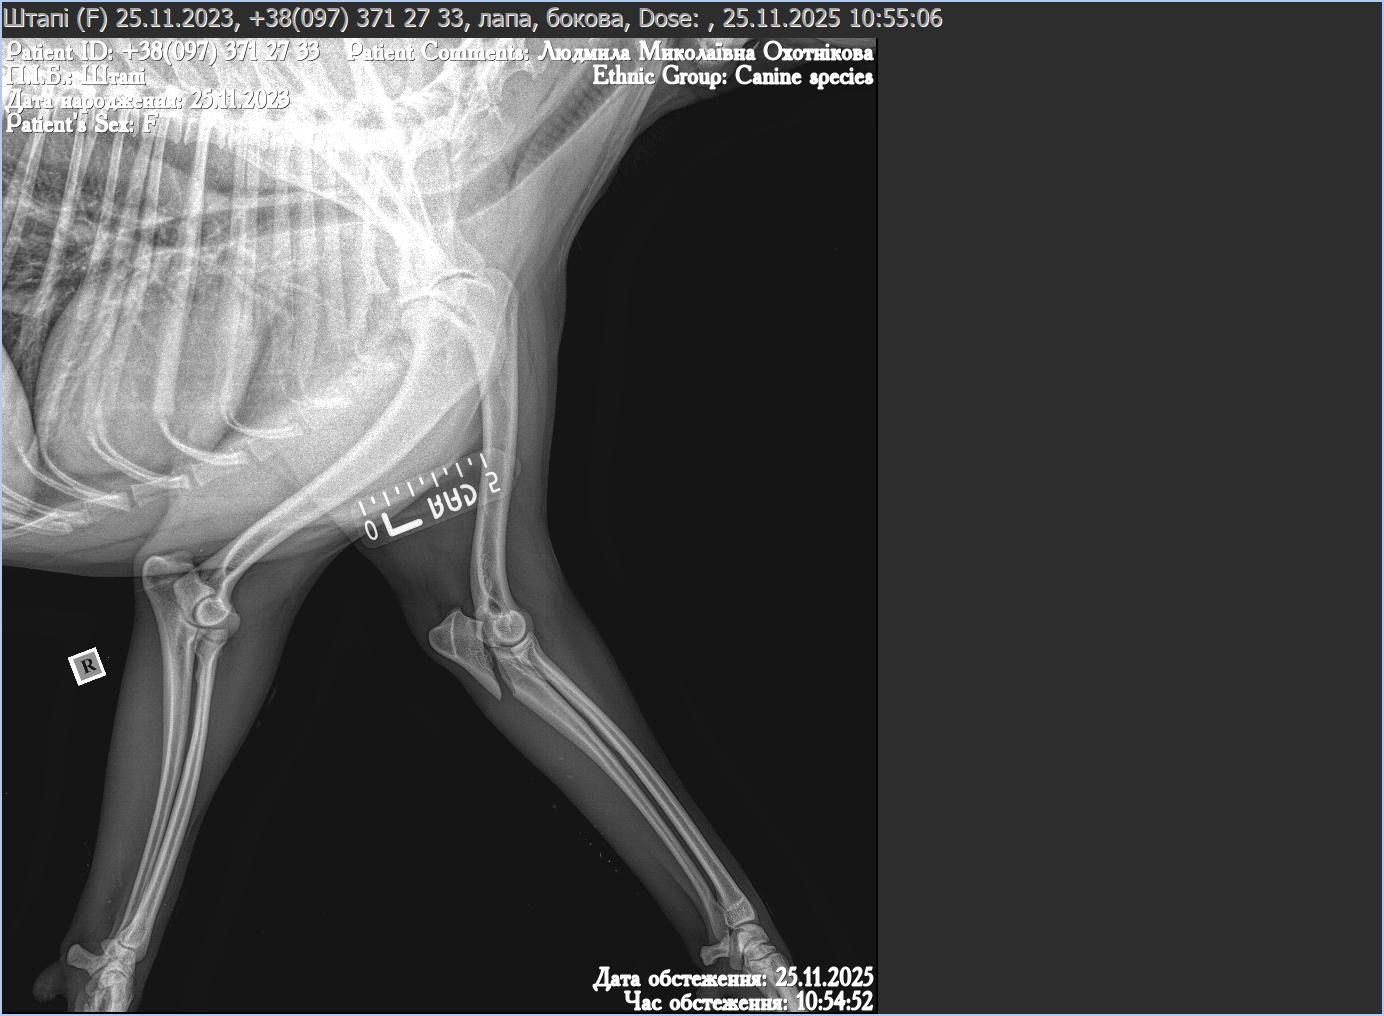

Kilka dni temu, podczas wykonywania obowiązków, Sztapik uległ poważnemu wypadkowi. Żołnierze natychmiast przewieźli go do kliniki, gdzie wykryto uszkodzenia narządów wewnętrznych, złamaną kość miednicy oraz złamaną przednią łapę. Jego stan był krytyczny, ale udało się go ustabilizować i uśmierzyć najostrzejszy ból.

Teraz przed nim długi proces leczenia. Potrzebna jest skomplikowana operacja, pełna diagnostyka, USG, badania kontrolne i stała obserwacja, bo przy takich obrażeniach każdy dzień może przynieść nowe komplikacje. Po zabiegu rozpocznie się rehabilitacja, która może potrwać wiele tygodni lub nawet miesięcy. Sztapik będzie uczył się chodzić od nowa, a jego ciało będzie wymagało systematycznego odciążania, ćwiczeń i specjalistycznej opieki.